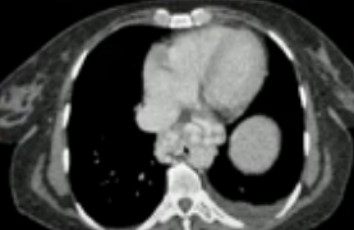

Цирроз печени на КТ с контрастом

Примеры изменений паренхимы железы в зависимости от типа процесса

КТ признаки цирроза печени

Норма и патология

Критерием для постановки диагноза рассматривают:

- увеличение/уменьшение размеров печени на КТ;

- бугристые контуры органа (при крупноузловой форме цирроза);

- визуализацию расширенных множественных септ — фиброзных перегородок;

- спленомегалию;

- варикозное расширение вен в области интереса, формирование коллатерального кровообращения, артерио-портальных и порто-венозных шунтов;

- фиброз, жировые изменения;

- сморщивание правой доли и гипертрофия левой — симптом “целующихся печени и селезенки” типичен для поздней стадии.

Выраженная адвентициальная сеть без возможности различить стенку пищевода

Расширенные сосуды дифференцируют с увеличенными лимфоузлами, что возможно при выполнении многоплоскостных реконструкций изображений и использования ангиорежимов.